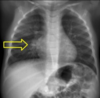

A

• Quiste

• Caverna

• Bulla

• Bronquiectasia